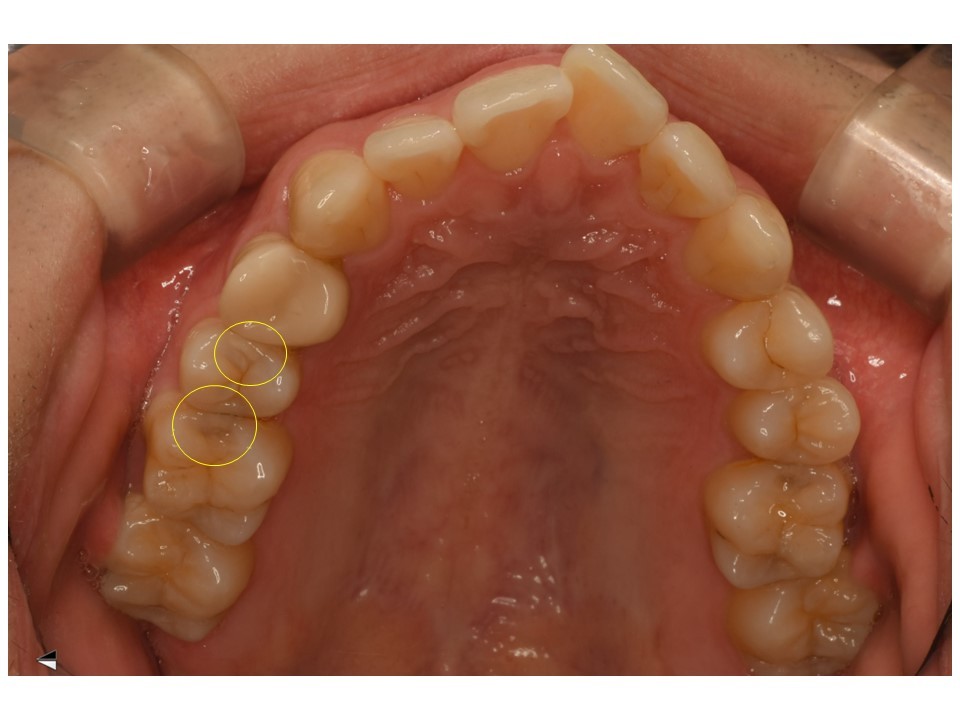

黄色の〇の場所にむし歯があります。

黄色〇のほかに、白い〇のところにもう蝕が確認されました。

こちらは現時点で基準以下の大きさと判断して、非切削治療を選択しました。